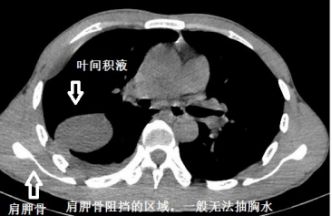

第四章 胸水的靠山

有靠山,不好惹,肩胛骨罩着的胸水,抽不到很正常!